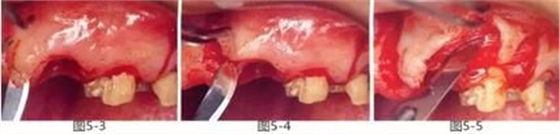

圖5-6,7

使用手術(shù)刀、7號(hào)牙齦刀、11號(hào)牙齦刀、咬骨鉗,盡可能將牙根周圍的軟組織進(jìn)行整體切除。